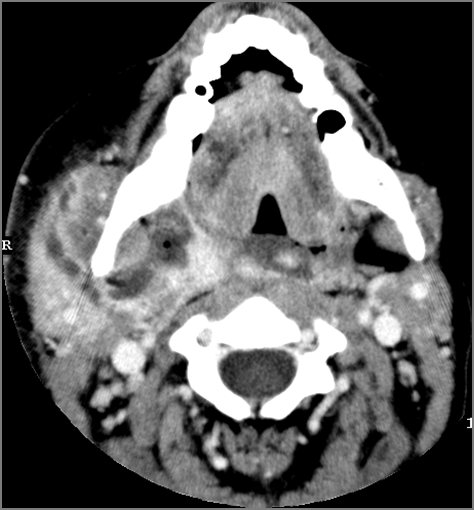

9 month old male presenting to the emergency room with poor feeding, fever, respiratory distress and possible retropharyngeal abscess or suppurative retropharyngeal adenitis.Exam

There is reactive retropharyngeal lymphadenopathy. |

Yes | NA |

There is suppurative retropharyngeal lymphadenopathy. |

If there is suppurative retropharyngeal adenopathy what is the maximum short axis dimension of the largest suppurative node. Measurement |

< 2cm | NA |

There is edema/abscess within the adjacent parapharyngeal and retropharyngeal spaces. |

Pharyngitis with suppurative retropharyngeal adenitis.